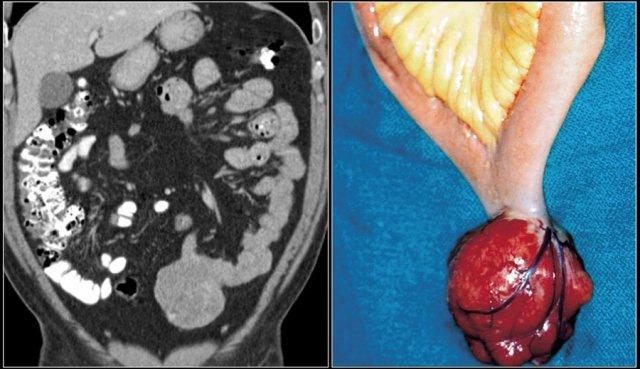

Điển hình, GIST là một khối giới hạn rõ, phát triển ngoài lòng ruột (exophytic), ngấm thuốc không đồng nhất và có ranh giới rõ ràng với mạc treo ruột.

Tắc ruột hiếm gặp vì GIST không xâm lấn toàn bộ chu vi thành ruột, khác với ung thư biểu mô tuyến (adenocarcinoma).

Khác với u carcinoid, tổn thương nguyên phát trong GIST thường có kích thước lớn.

Cả GIST và u lympho đều có thể gây giãn phình dạng túi (aneurysmal dilation) của lòng ruột.

Di căn gan thường tăng sinh mạch (hypervascular) và có thể bị bỏ sót nếu chỉ chụp CT đơn thì tĩnh mạch cửa.

Di căn hạch bạch huyết thường không gặp.